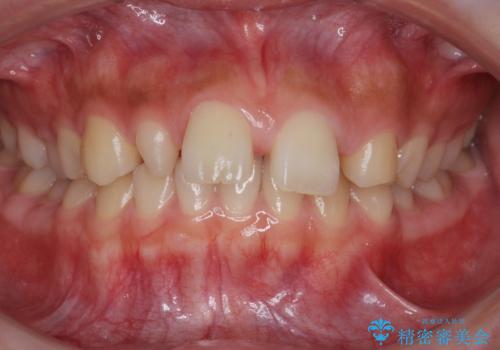

前歯が出っ歯ですきっ歯 抜かずに前歯を見た目良く

- 前歯の並びを主訴に来院。

前歯が出ており、また、左上の側切歯が1本生まれつき少ない状態でした。

また、右の奥歯の関係も上が前にある状態で大きくずれていました。